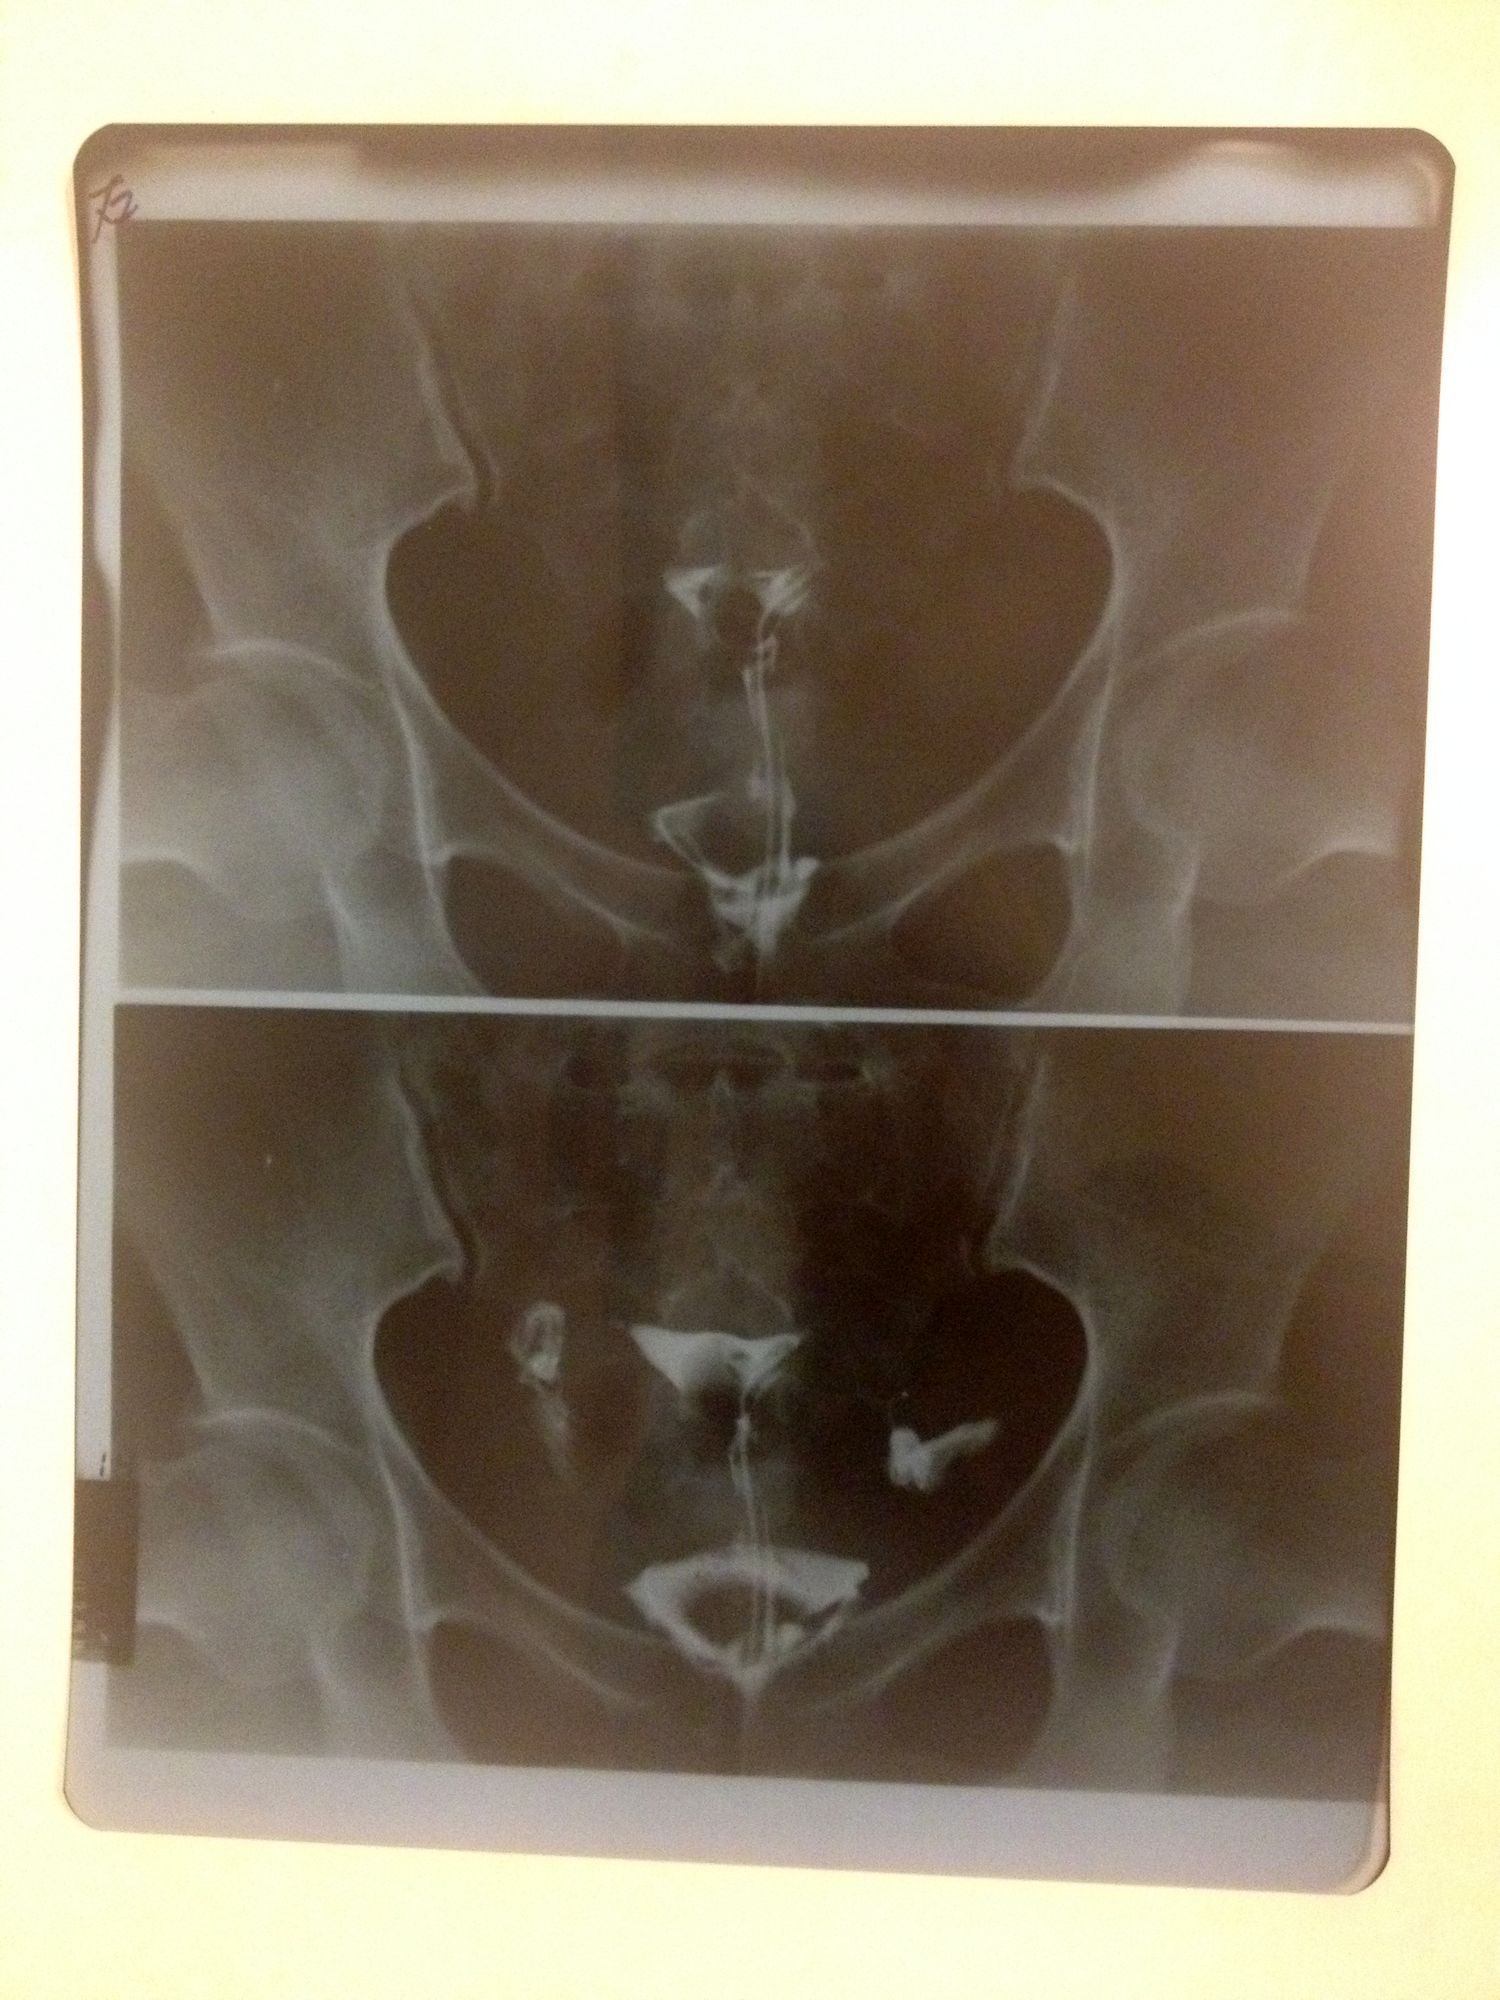

输卵管伞端粘连远端堵塞如何治疗 做造影的医生说你要快就直接宫腔镜,中药吃几年未必有效,毕竟30多了,然后带着片子回医院看,医生说你直接试管吧,堵成这样没用了。换了家民营医院,医生说你没有严重到只能做试管的地步,试管成功率低,等待时间长。然后她给我看了很多病人在试管无效的情况下在她那里做了腹腔镜然后怀孕的病例。身边有个朋友之前也是输卵管堵塞做了腹腔镜,短期没有效果就直接试管了,可是试管失败了,但是没过多久居然怀孕了,可能还是腹腔镜的关系?不知道到底该怎么办,请医生帮我看看我这个到底应该做什么? 点击展开 匿名用户 2014-08-06 12:27 为您推荐: 其他回答 你好,这个时候是要自己注意去医院里检查一下的呢,这个情况是要让医生给好好的处理一下的啊 生活还在继续66 2014-08-07 16:02 相关问题 输卵管伞端未显影是不是就是堵塞或者粘连了? 右侧输卵管远端积水怎,左侧伞端粘连 请问该怎么治疗 急急急 双侧输卵管伞端粘连,远端增粗,用药治疗怀孕的几率有吗??

做造影的医生说你要快就直接宫腔镜,中药吃几年未必有效,毕竟30多了,然后带着片子回医院看,医生说你直接试管吧,堵成这样没用了。换了家民营医院,医生说你没有严重到只能做试管的地步,试管成功率低,等待时间长。然后她给我看了很多病人在试管无效的情况下在她那里做了腹腔镜然后怀孕的病例。身边有个朋友之前也是输卵管堵塞做了腹腔镜,短期没有效果就直接试管了,可是试管失败了,但是没过多久居然怀孕了,可能还是腹腔镜的关系?不知道到底该怎么办,请医生帮我看看我这个到底应该做什么?